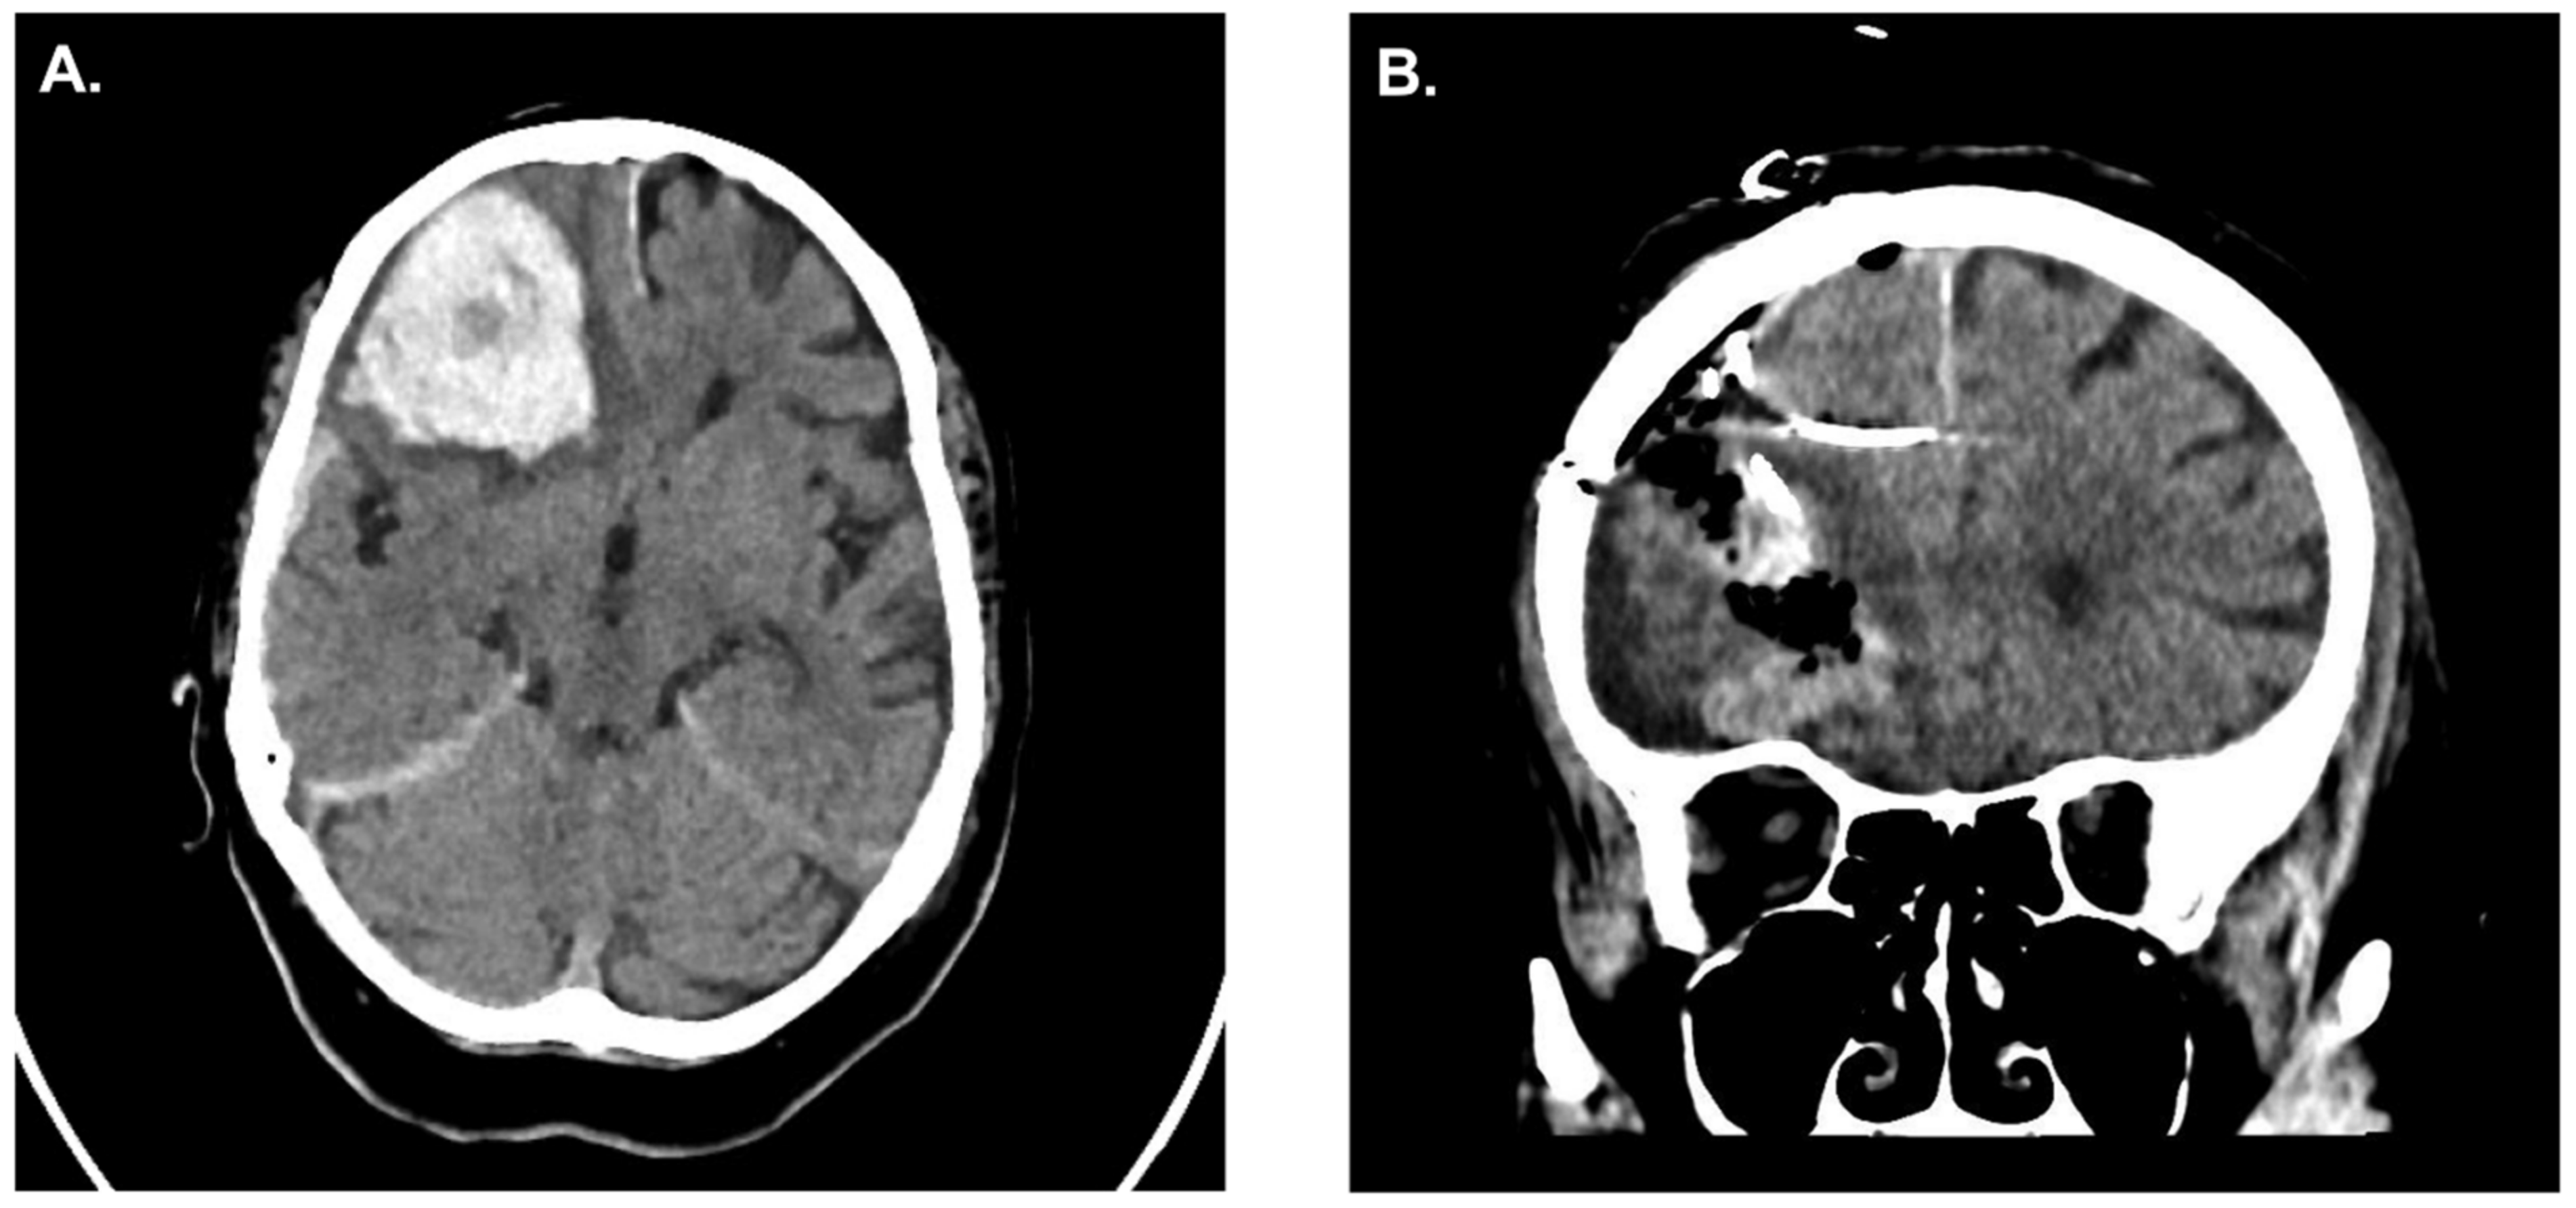

Case Illustration